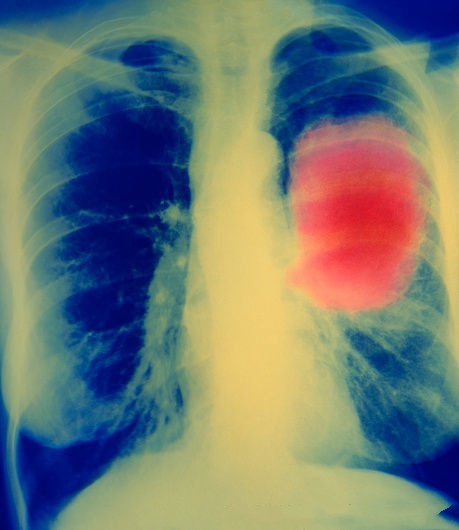

Lung cancer. Coloured X-ray image showing an oval-shaped carcinoma (orange) in the left lung (right of image). Lung cancer is a very common primary malignant tumour; it is commoner in men than women and has a clear association with cigarette smoking. There are several types of lung cancer, the most common being squamous cell carcinoma, adenocarcinoma and large cell carcinoma; generally, it is not possible to identify the type of cancer only from a radiological investigation. If the cancer is diagnosed at an early stage, pneumonectomy (removal of the lung) is performed.